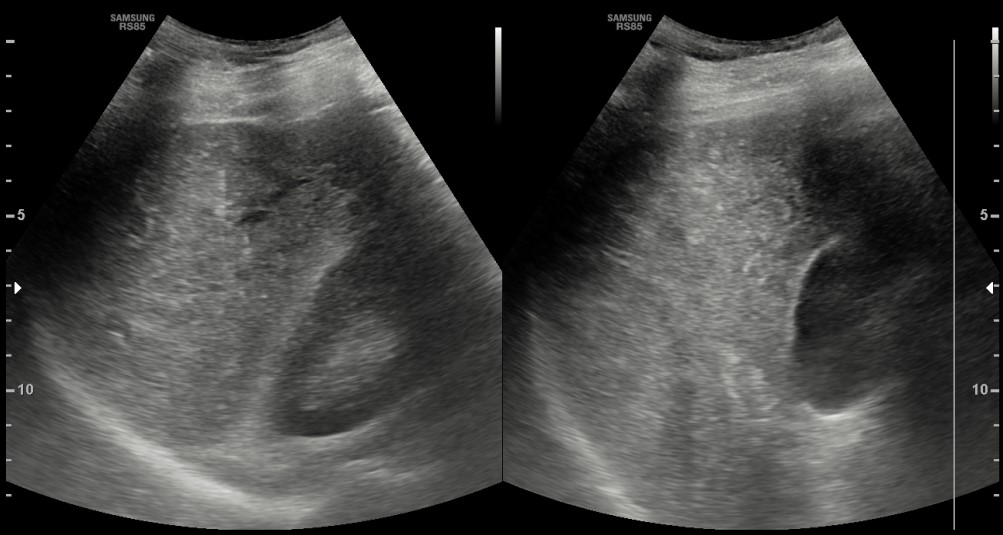

[366,Hepatobiliary [HB]] 62/M,Abnormal finding on upper abdominal ultrasonography during a health check-up

Hepatobiliary [HB]

US,

What is the most likely diagnosis?